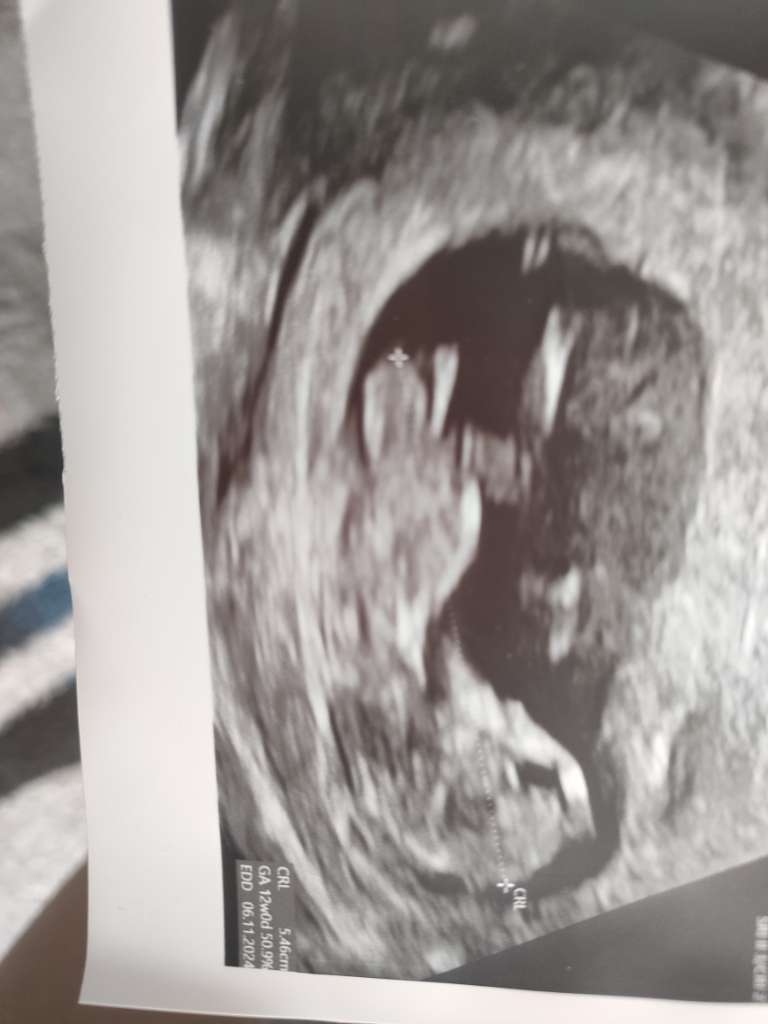

Który tydzień?Witam serdecznie, czy widać na tych Usg płeć dziecka ?

12+4Który tydzień?

11+6 to za wczesnie na ocenę wyrostka płciowegoDzień dobry. Czy na tych zdjęciach widać już płeć? Jak myślicie ?![]()